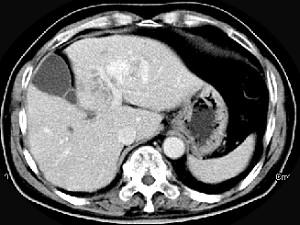

问题 男性,54岁,右上腹部不适,CT检查如图,最可能的诊断是 ( )

选项 A、肝血管瘤伴肝脓肿 B、肝血管瘤伴炎性肉芽肿 C、肝多发血管瘤 D、肝血管瘤伴肝癌 E、肝血管瘤伴转移瘤

答案 C